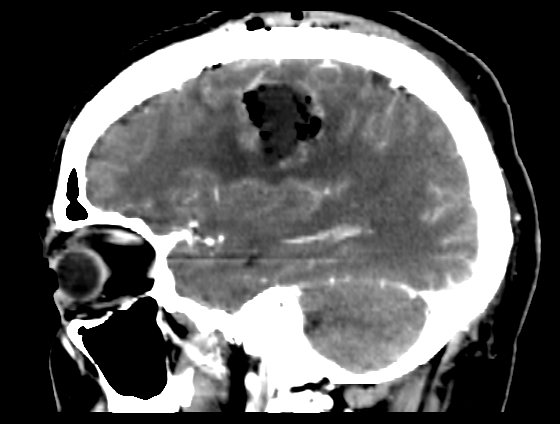

Resezione microchirurgica di tumore cerebrale (glioma alto grado cortico-sottocorticale) frontale dx